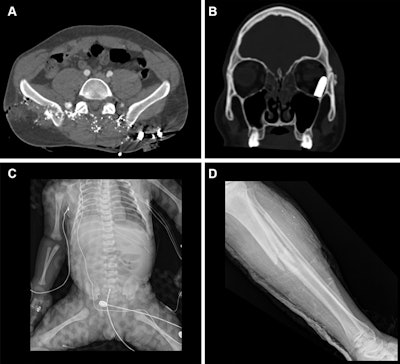

Representative injuries in patients from the mass casualty incident of October 7, 2023. (A) Axial CT scan at the pelvic level in a 34-year-old male patient shows multiple shrapnel fragments in the pelvis, resulting in fractures of the pelvic bones and lumbar vertebrae (not visible on this image). (B) Coronal reconstruction of a head CT scan in a 20-year-old male patient shows penetrating trauma to the left eyeball with a retained bullet in the orbital cavity. (C) Radiograph of a fetus delivered by emergency cesarean section from a critically injured mother shows a left pneumothorax and catheter in place. (D) Radiograph in a 25-year-old female patient shows a comminuted fracture in the tibial metaphysis with fragment displacement and multiple bony fragments in the surrounding soft tissues.Representative injuries in patients from the mass casualty incident of October 7, 2023. (A) Axial CT scan at the pelvic level in a 34-year-old male patient shows multiple shrapnel fragments in the pelvis, resulting in fractures of the pelvic bones and lumbar vertebrae (not visible on this image). (B) Coronal reconstruction of a head CT scan in a 20-year-old male patient shows penetrating trauma to the left eyeball with a retained bullet in the orbital cavity. (C) Radiograph of a fetus delivered by emergency cesarean section

from a critically injured mother shows a left pneumothorax and catheter in place. (D) Radiograph in a 25-year-old female patient shows a comminuted fracture in the tibial metaphysis with fragment displacement and multiple bony fragments in the surrounding soft tissues.